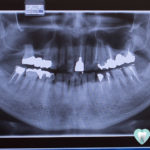

治療対象の歯並び・噛み合わせ

矯正歯科治療の対象となる不正な歯並びや、噛み合わせをご紹介します。